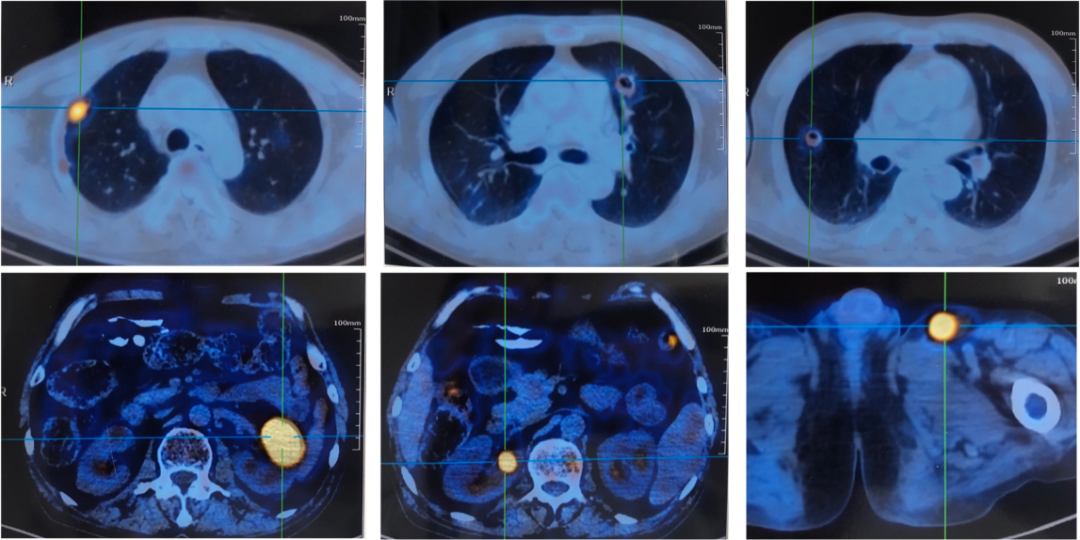

外院PET-CT(图2):

图2:PET-CT

外院支气管镜下可见大量脓性分泌物,BALF病原学示多重耐药鲍曼不动杆菌、屎肠球菌、粪肠球菌、构巢曲霉等多种病原菌;

先后应用万古霉素、替加环素、米诺环素、伏立康唑、哌拉西林舒巴坦等治疗效果不佳。